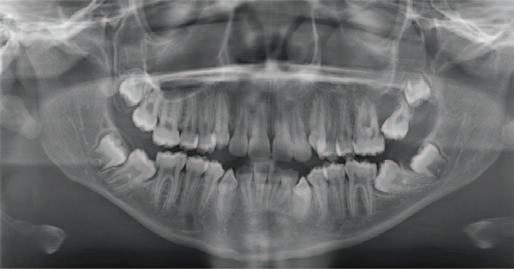

Journal of the Irish dental association by Th!nk Media - Issuu